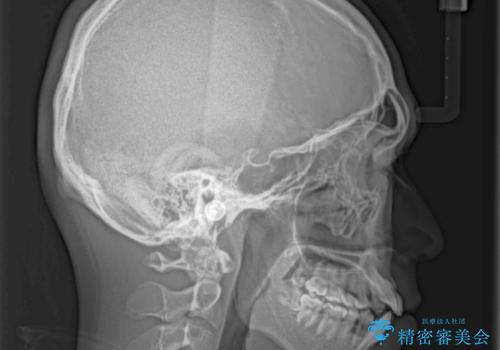

- 前歯のデコボコと若干口元が突出していることを気にして来院された患者様です。

全体的に軽微な叢生が認められ、口元もやや前方に突出していたため、インビザラインでのIPR(歯と歯の間を削る)と歯列全体の後方移動によって歯並びを整えることとしました。

上下ともに歯列の幅が狭かったため、側方に拡大することで前歯のデコボコや突出感を解消するためのスペースを獲得することができました。